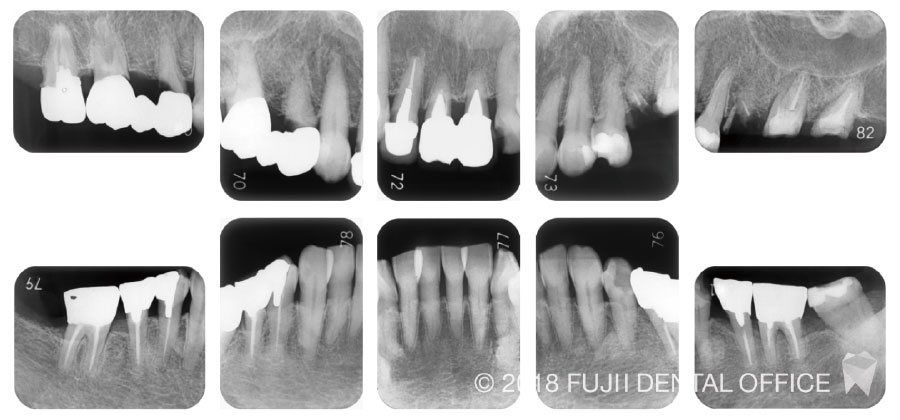

咬合再構成症例

主訴

「審美不良」「咀嚼困難」

目的

不良補綴装置による審美障害・咀嚼障害の回復

治療内容

抜歯+インプラント(抜歯即時埋入、骨造成、ソケットリフト) +審美情報・運動路採得+咬合再構成

副作用・リスク

術後疼痛・腫脹、顎関節症

治療期間

18ヶ月

費用[税抜]

5,700,000円

【内訳】

- インプラント: 350,000円×9本

- 骨造成: 70,000円×2カ所

- ソケットリフト: 50,000×3カ所

- プロビジョナルレストレーション:80,000円×2回

- ジルコニアセラミック冠: 150,000円×14本

目的: 不良補綴装置による審美障害・咀嚼障害の回復

治療内容: 抜歯+インプラント(抜歯即時埋入、骨造成、ソケットリフト) +審美情報・運動路採得+咬合再構成

副作用・リスク: 術後疼痛・腫脹、顎関節症

治療期間: 18カ月

費用[税抜]: 5,700,000円

【内訳】 ・インプラント: 350,000円×9本

・骨造成: 70,000円×2カ所

・ソケットリフト: 50,000×3カ所

・プロビジョナルレストレーション: 80,000円×2回

・ジルコニアセラミック冠: 150,000円×14本